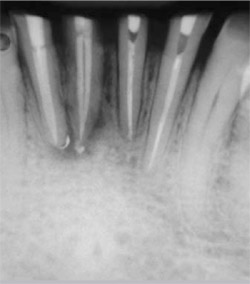

A 53-year-old woman who had had previous root canal treatment and a prefabricated post-and-core restoration on tooth No. 8 (Figure 2) was referred to the endodontic clinic because of periapical radiolucence. The patient reported throbbing pain in the maxillary central incisors region for several weeks. The apical diagnosis was chronic apical periodontitis because of root canal failure. The post was removed using ultrasonic energy (Figure 3 and Figure 4).

| Figure 3 Metal post removed with ultrasonic energy from failed restoration. | Figure 4 Radiograph of tooth No. 8 showing canal space after post was removed using ultrasonic energy. | ||||||||